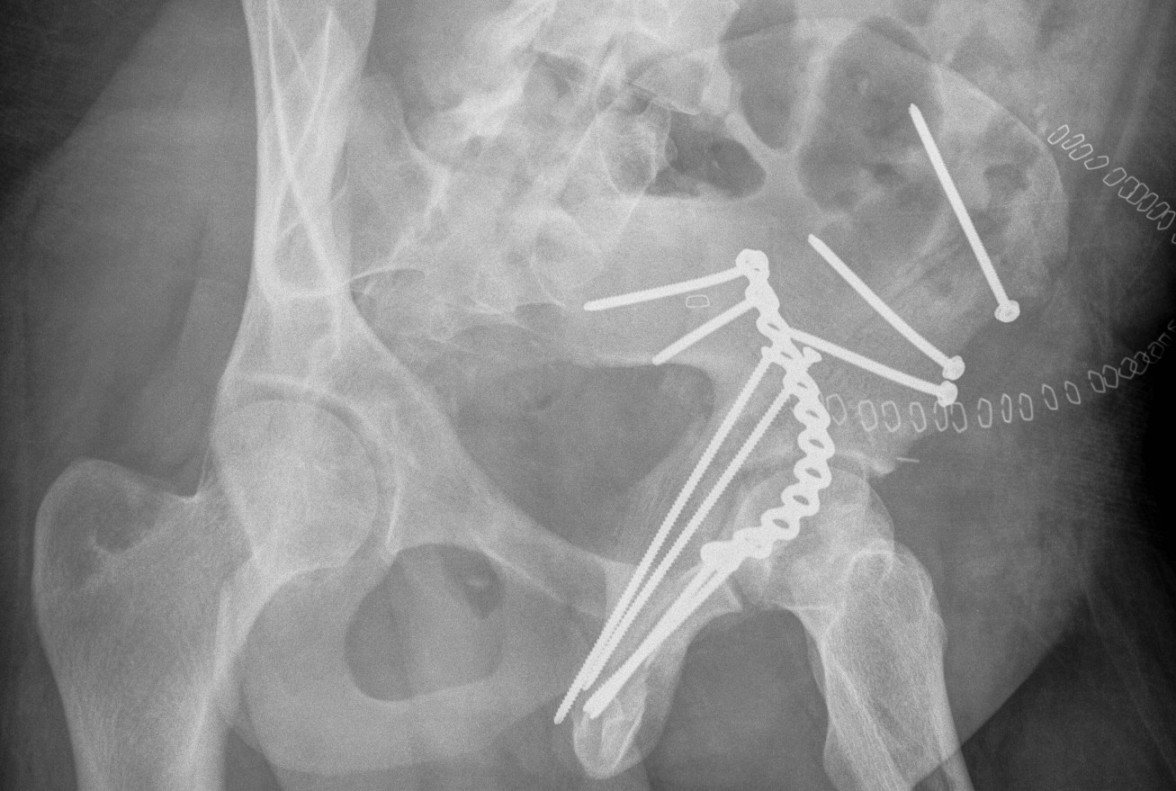

Posterior Column & Wall Fracture

Reduction

- often indirect

- buttress plate from Ischial Tuberosity to Ilium

- contour or use pre-contoured

- screws at plate extremities

- often 2 parallel plates if wall and column fracture

II to ensure screws not in acetabulum